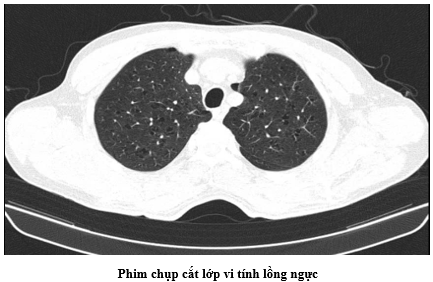

- Chụp Cắt lớp vi tính lồng ngực: Hình ảnh nốt đặc thùy trên phổi trái và thùy giữa phổi phải. Nốt vôi hóa thùy dưới phổi phải. Chưa phát hiện tổn thương ác tính